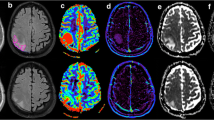

The measured normalised peritumoural rCBV values of the GBM (total number of slices analysed n = 218; 1.17 ± 0.32; mean ± SD) were significantly higher than in the metastases (number of slices n = 127; 0.78 ± 0.17) with p < 0.001 (Figs. 2 and 3).

Considering the averaged rCBV of the entire peritumoural area for each tumour, the averaged rCBV values of the GBM ranged from 0.67 to 1.88 (median 1.14) whereas the averaged rCBV for metastases ranged from 0.57 to 1.15 (median 0.76). There was only one single patient with an increased averaged peritumoural rCBV value (1.15) in the group of metastases. For GBM, there were seven patients with a lowered averaged peritumoural rCBV value <1.

The results of the present study indicate that peritumoural rCBV is feasible to discriminate metastases from GBM. The cutoff value of 1.0 for the peritumoural rCBV values yields a high negative predictive value and a high specificity to detect metastases. The threshold of 1.0 was found to be optimal by another study investigating solitary brain tumours in the region of maximal rCBV [37]. We used this cutoff value following the concept that tumour cell infiltration beyond the contrast-enhancing tumour border induces rCBV increase, and hence rCBV increase should be detected in the peritumoural area of GBM (Fig. 1), but not of non-infiltrating metastases (normalised rCBV value related to rCBV value of normal-appearing brain tissue ≤1.0). However, peritumoural rCBV decrease was found in both metastases and in GBM (Figs. 4 and 5). Visual inspection of the rCBV parameter maps was even more sensitive in delineating peritumoural rCBV increase because averaging heterogeneous rCBV values of all voxels within a ROI may equalise small areas of rCBV increase. However, we performed the ROI method to get a more objective analysis.

In contrast, we considered that the peritumoural area has a three-dimensional shape, delineating an approximately 15-mm-thick rim-like region on all slices depicting the contrast-enhancing tumour without concerning T2-weighted signal alterations. According to this analysis, the mean peritumoural rCBV ratios of GBM and metastases (1.17 ± 0.32 and 0.78 ± 0.17, respectively) are within the lower range of the values described by previous studies (0.31 ± 0.12–2.33 ± 1.61 for high-grade gliomas and 0.39 ± 0.19–0.97 ± 0.09 for metastases) [5, 9, 12, 17].